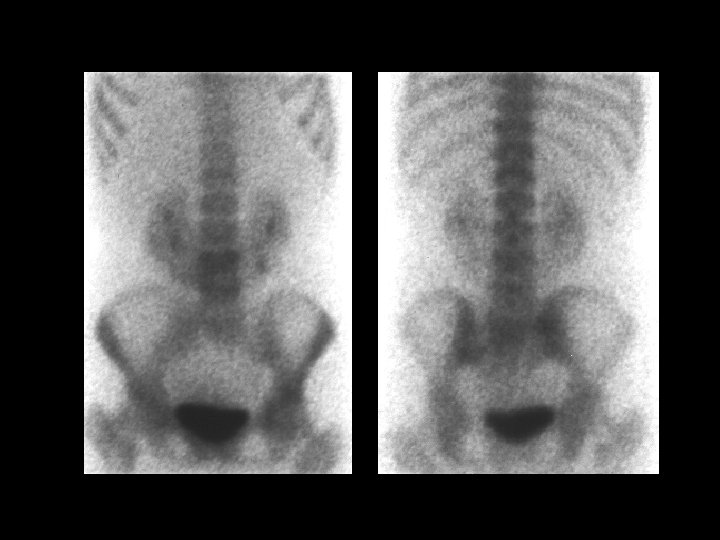

Osteopetrosis • • • Tc-99 m sulfur colloid, i. v. intense liver/spleen uptake, little or none in the bone marrow Trabecular --> compact bone --> Diffuse inc bone density Anemia w/extramedullary hematopoiesis ddx: (adults) – – – myelofibrosis sclerotic metastases renal osteodystrophy multiple myeloma Paget’s